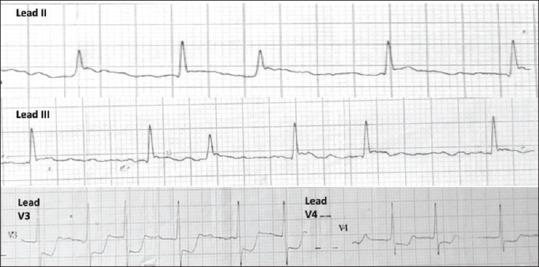

Cardiogenic pulmonary edema usually presents with characteristic clinical features and bilateral infiltrates on the chest radiograph. Rarely, pulmonary edema may manifest unilaterally, leading to a mistaken diagnosis of a primary lung pathology. We present a 30-year-old man who developed acute coronary syndrome following an overdose of alprazolam. He developed breathlessness with unilateral infiltrates on the chest radiograph. Echocardiography revealed regional wall motion abnormalities related to underlying ischemia and acute mitral regurgitation with an eccentric jet. Besides, he had significant impairment of left ventricular systolic function. His coronary angiogram revealed a slow-flow phenomenon in the right coronary and left anterior descending artery territories. Ischemia-related dysfunction of the posterolateral papillary muscle probably led to a floppy posterior mitral leaflet and an eccentrically directed regurgitant jet, leading to unilateral pulmonary edema. He was commenced on dual antiplatelet therapy, heparin infusion, atorvastatin, frusemide, and ramipril, following which he showed gradual clinical improvement along with resolution of the radiological infiltrates. His left ventricular function improved, and the mitral valve function normalized on echocardiography within a week.

心源性肺水肿通常表现为特征性临床症状及胸部X线片显示双侧浸润影。肺水肿很少单侧出现,从而导致误诊为原发性肺部疾病。我们报告一名30岁男性,在过量服用阿普唑仑后发生急性冠状动脉综合征。他出现呼吸困难,胸部X线片显示单侧浸润影。超声心动图显示与潜在缺血相关的节段性室壁运动异常以及伴有偏心反流束的急性二尖瓣反流。此外,他的左心室收缩功能严重受损。其冠状动脉造影显示右冠状动脉和左前降支动脉区域存在血流缓慢现象。后外侧乳头肌的缺血相关功能障碍可能导致二尖瓣后叶脱垂及偏心反流束,进而导致单侧肺水肿。他开始接受双联抗血小板治疗、肝素输注、阿托伐他汀、呋塞米和雷米普利治疗,之后临床症状逐渐改善,放射学浸润影也逐渐消退。一周内,他的左心室功能改善,超声心动图显示二尖瓣功能恢复正常。